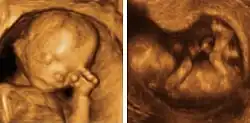

Ecografía 3D y 4D

En los últimos tiempos se ha podido ver una revolución en el campo de la medicina materno-fetal. Esa revolución, además, no solo ha afectado a la medicina en sí misma, sino que ha aportado a la sociedad la posibilidad de establecer una unión emocional con los neonatos mucho más profunda de lo que hasta ahora se creía posible, gracias a una calidad de imagen que permite ver el aspecto del futuro bebé en fotografía (3D) o en imagen en movimiento (4D).

Para lograrlo, mediante el ecógrafo, se emiten los ultrasonidos en cuatro ángulos y direcciones, pasando el emisor suavemente por la barriga del paciente, a la cual se le ha aplicado previamente un gel para mejorar la eficiencia del proceso. Los ultrasonidos rebotan y son captados por el ordenador, que procesa automáticamente la información para reproducir en la pantalla la imagen a tiempo real del bebé.